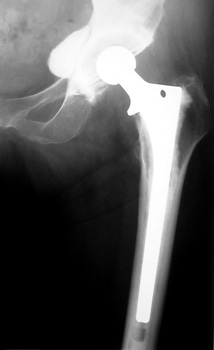

Cement extravasation in the pelvis from through defect in the

acetabulum.